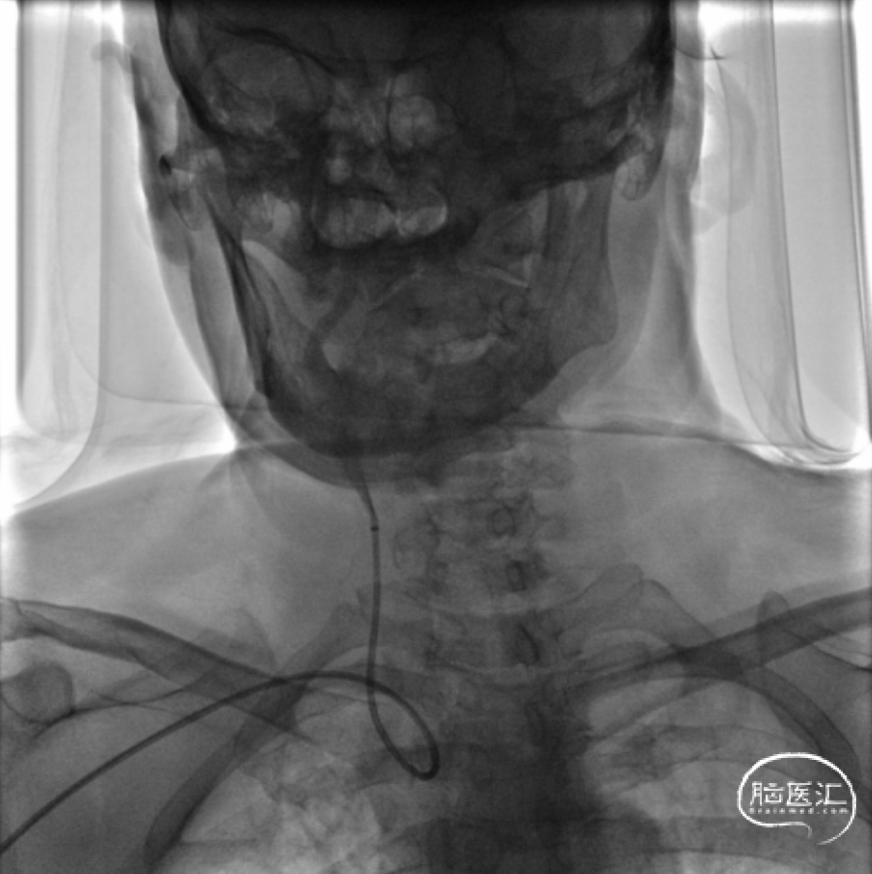

dTRA-6F薄壁鞘-置入泥鳅导丝交换后引入易介80cm-088薄壁长鞘

撤除内衬后088薄壁长鞘保持稳定未打折

输送950Wallstent支架过程中系统稳定未出现移位